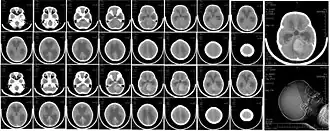

| Tomografia de um meduloblastoma em uma menina de 6 anos, causando hidrocefalia. | |